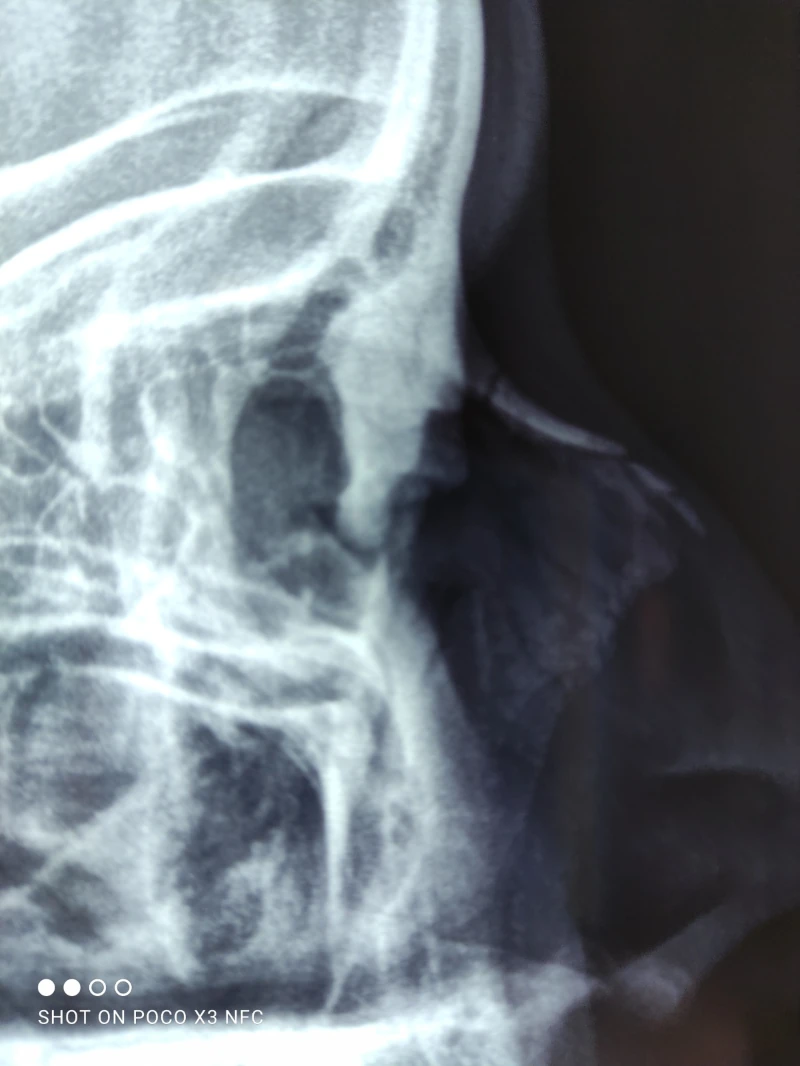

04. Sinusitis (infección de los senos paranasales)

06. Fractura nasal

08. Deformidad del tabique